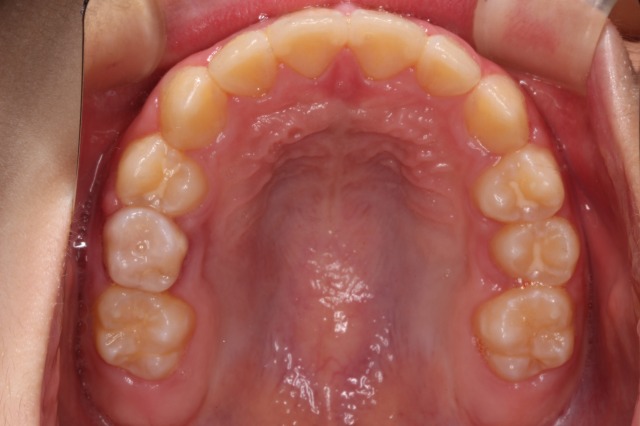

出っ歯の改善

治療前

治療後

| 主訴 | 出っ歯と上の前歯が下の歯に重なることを気にして来院 |

| 治療期間 | 10ヶ月 |

| 費用 | 440,000円(税込) |

| 治療内容 | 専用マウスピースの装着(日中1~2時間と就寝時) 筋機能療法(正しい呼吸、舌の位置、飲み込み方のトレーニング) |